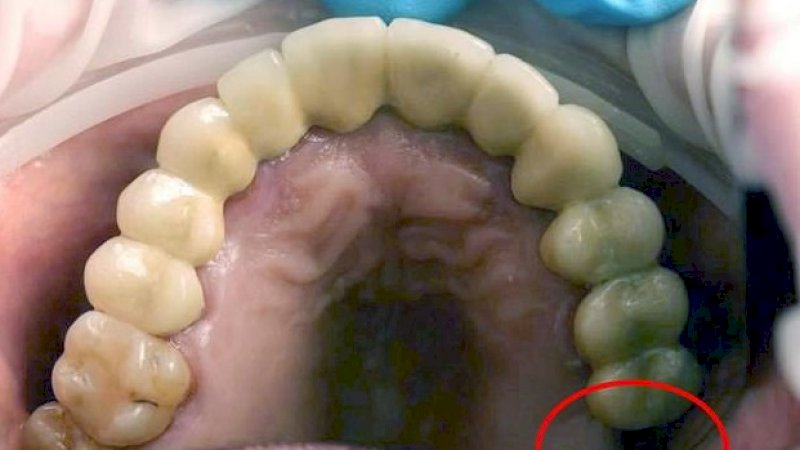

Menurut pemeriksaan, gigi geraham anak laki-laki itu telah hilang, dan diyakini bahwa itulah yang tumbuh di salah satu testisnya.

"Gigi itu molar kedua, atau ketujuh di rahang atas," kata pernyataan rumah sakit.

"Biasanya diganti oleh gigi permanen pada usia sepuluh hingga 12 tahun."